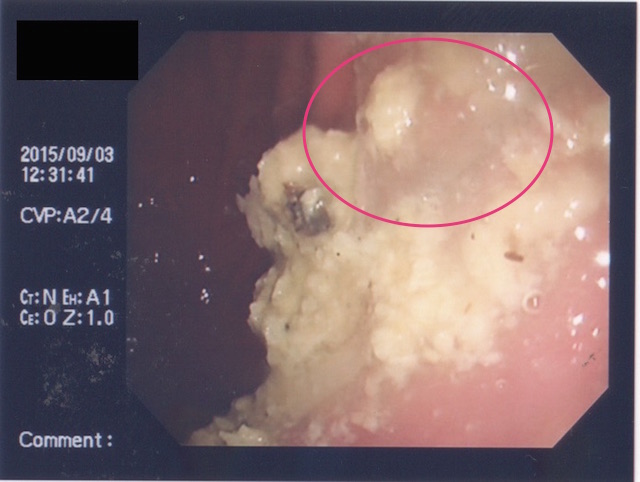

早速、内視鏡にて胃内を確認。すると、やはりありました。

しかも、ご丁寧に噛み砕かれていて複数個あります。。。(;´Д`)

内視鏡のポートより把持鉗子を挿入して異物を除去しながら、メガネのレンズのパズルをしていきました。無事パズル完成!!めでたしめでたし!!